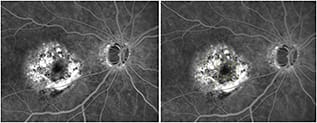

Figure 5. Color fundus photo (left) of an eye with circinate retinopathy that underwent previous laser photocoagulation following radiation for choroidal melanoma (black). Early-phase fluorescein angiography image (right) showing retinal scars from previous laser photocoagulation.

Figure 6. Late-phase fluorescein angiography image of the same eye in Figure 5, showing late leakage next to retinal scars from previous laser photocoagulation. The large yellow circle represents the “no treatment zone,” and the small yellow circles are target laser spots. A Navilas treatment plan (right) for grid laser, based on a retinal thickness map from an OCT scan of the same eye imported into the Navilas system, overlaid on the FA image. False color (red) shows retinal thickening, although overt leakage is absent on FA.